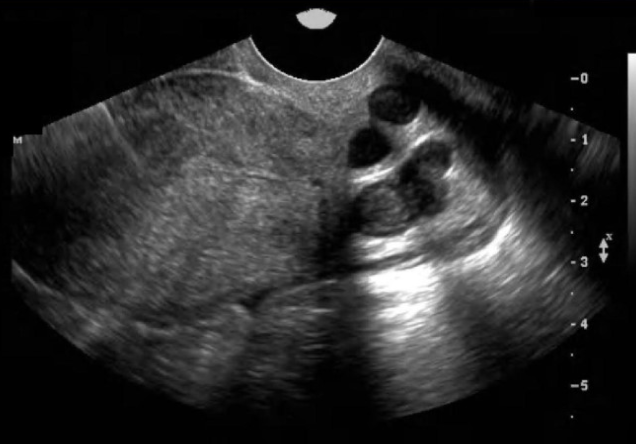

a) obtain a cross-section view of the umbilical cord insertion at the placenta + apply color doppler

b) obtain a transverse view of the fetal abd at the level of the kidneys + apply color doppler

c) obtain a transverse view of the fetal pelvis at the level of the bladder + apply color doppler

d) obtain a midline sagittal view of the fetus that includes the fetal bladder + apply color doppler